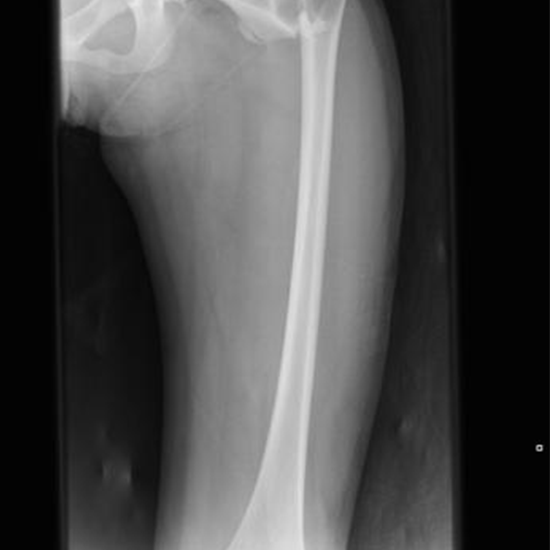

X-ray Left Femur AP/Lat

A femur X-ray displays the thigh bone (femur) and the surrounding soft tissues (skin and muscles).

When necessary, Femur X-rays can aid in surgical planning and post-operative evaluation. It can also detect bone cysts, tumors, and other illnesses, including bone infections in their latter stages.

A femur X-ray can assist physicians in determining the source of upper leg pain, limping, tenderness, edema, or deformity. It can detect a fracture, and once a fracture has been set, it can reveal whether the bone is aligned and has healed appropriately.